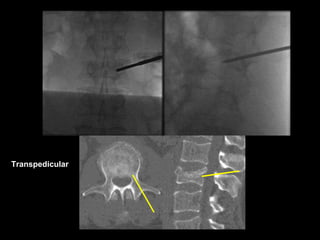

Transpedicular

Biopsy

Drill and Curette

Balloon Tamps

Cement Injection